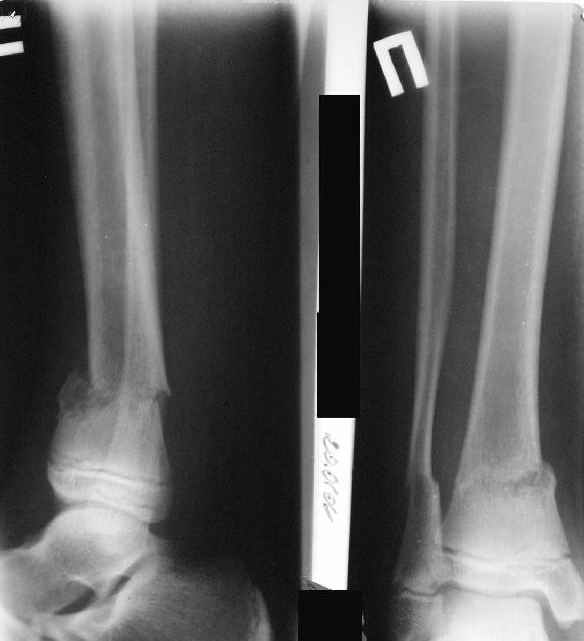

A>> Скелетное вытяжение за пяточную кость.

Вытяжение